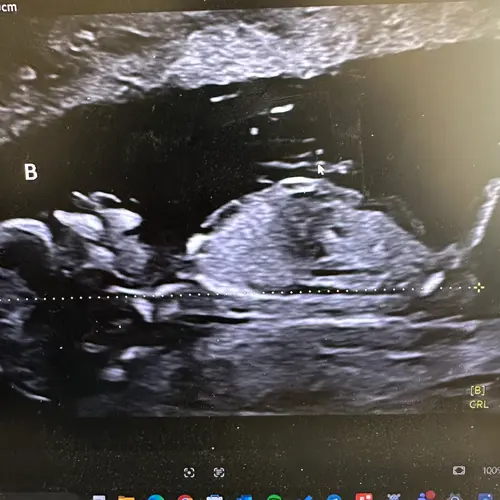

Is het hier wel beter op te zien?

Heb je nog een andere,

Deze misschien ?

Ook niet goed te zien helaas.. zie je niet rechts bij de beentjes op een andere foto een betere met een witte streep?